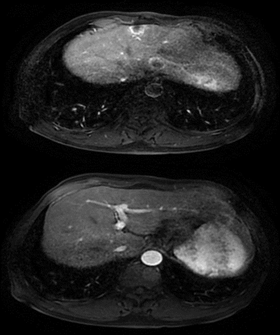

2018.6 肝脏MRI+C:肝左叶体积相对增大,肝裂增宽,肝内见多发异常信号影,大者直径约26mm,T1WI呈稍低信号,T2WI稍高信号,增强后环形强化。肝内、外胆管未见扩张。

2019.4 上腹部MR发现肝脏新发转移灶。

肝左叶缺如;肝裂增宽;右肝前上段近膈顶见一异常信号肿块,约15mm*20mm,T1WI呈稍低信号,T2WI稍高信号,增强后环形强化。右肝前上段近膈顶新发转移瘤。